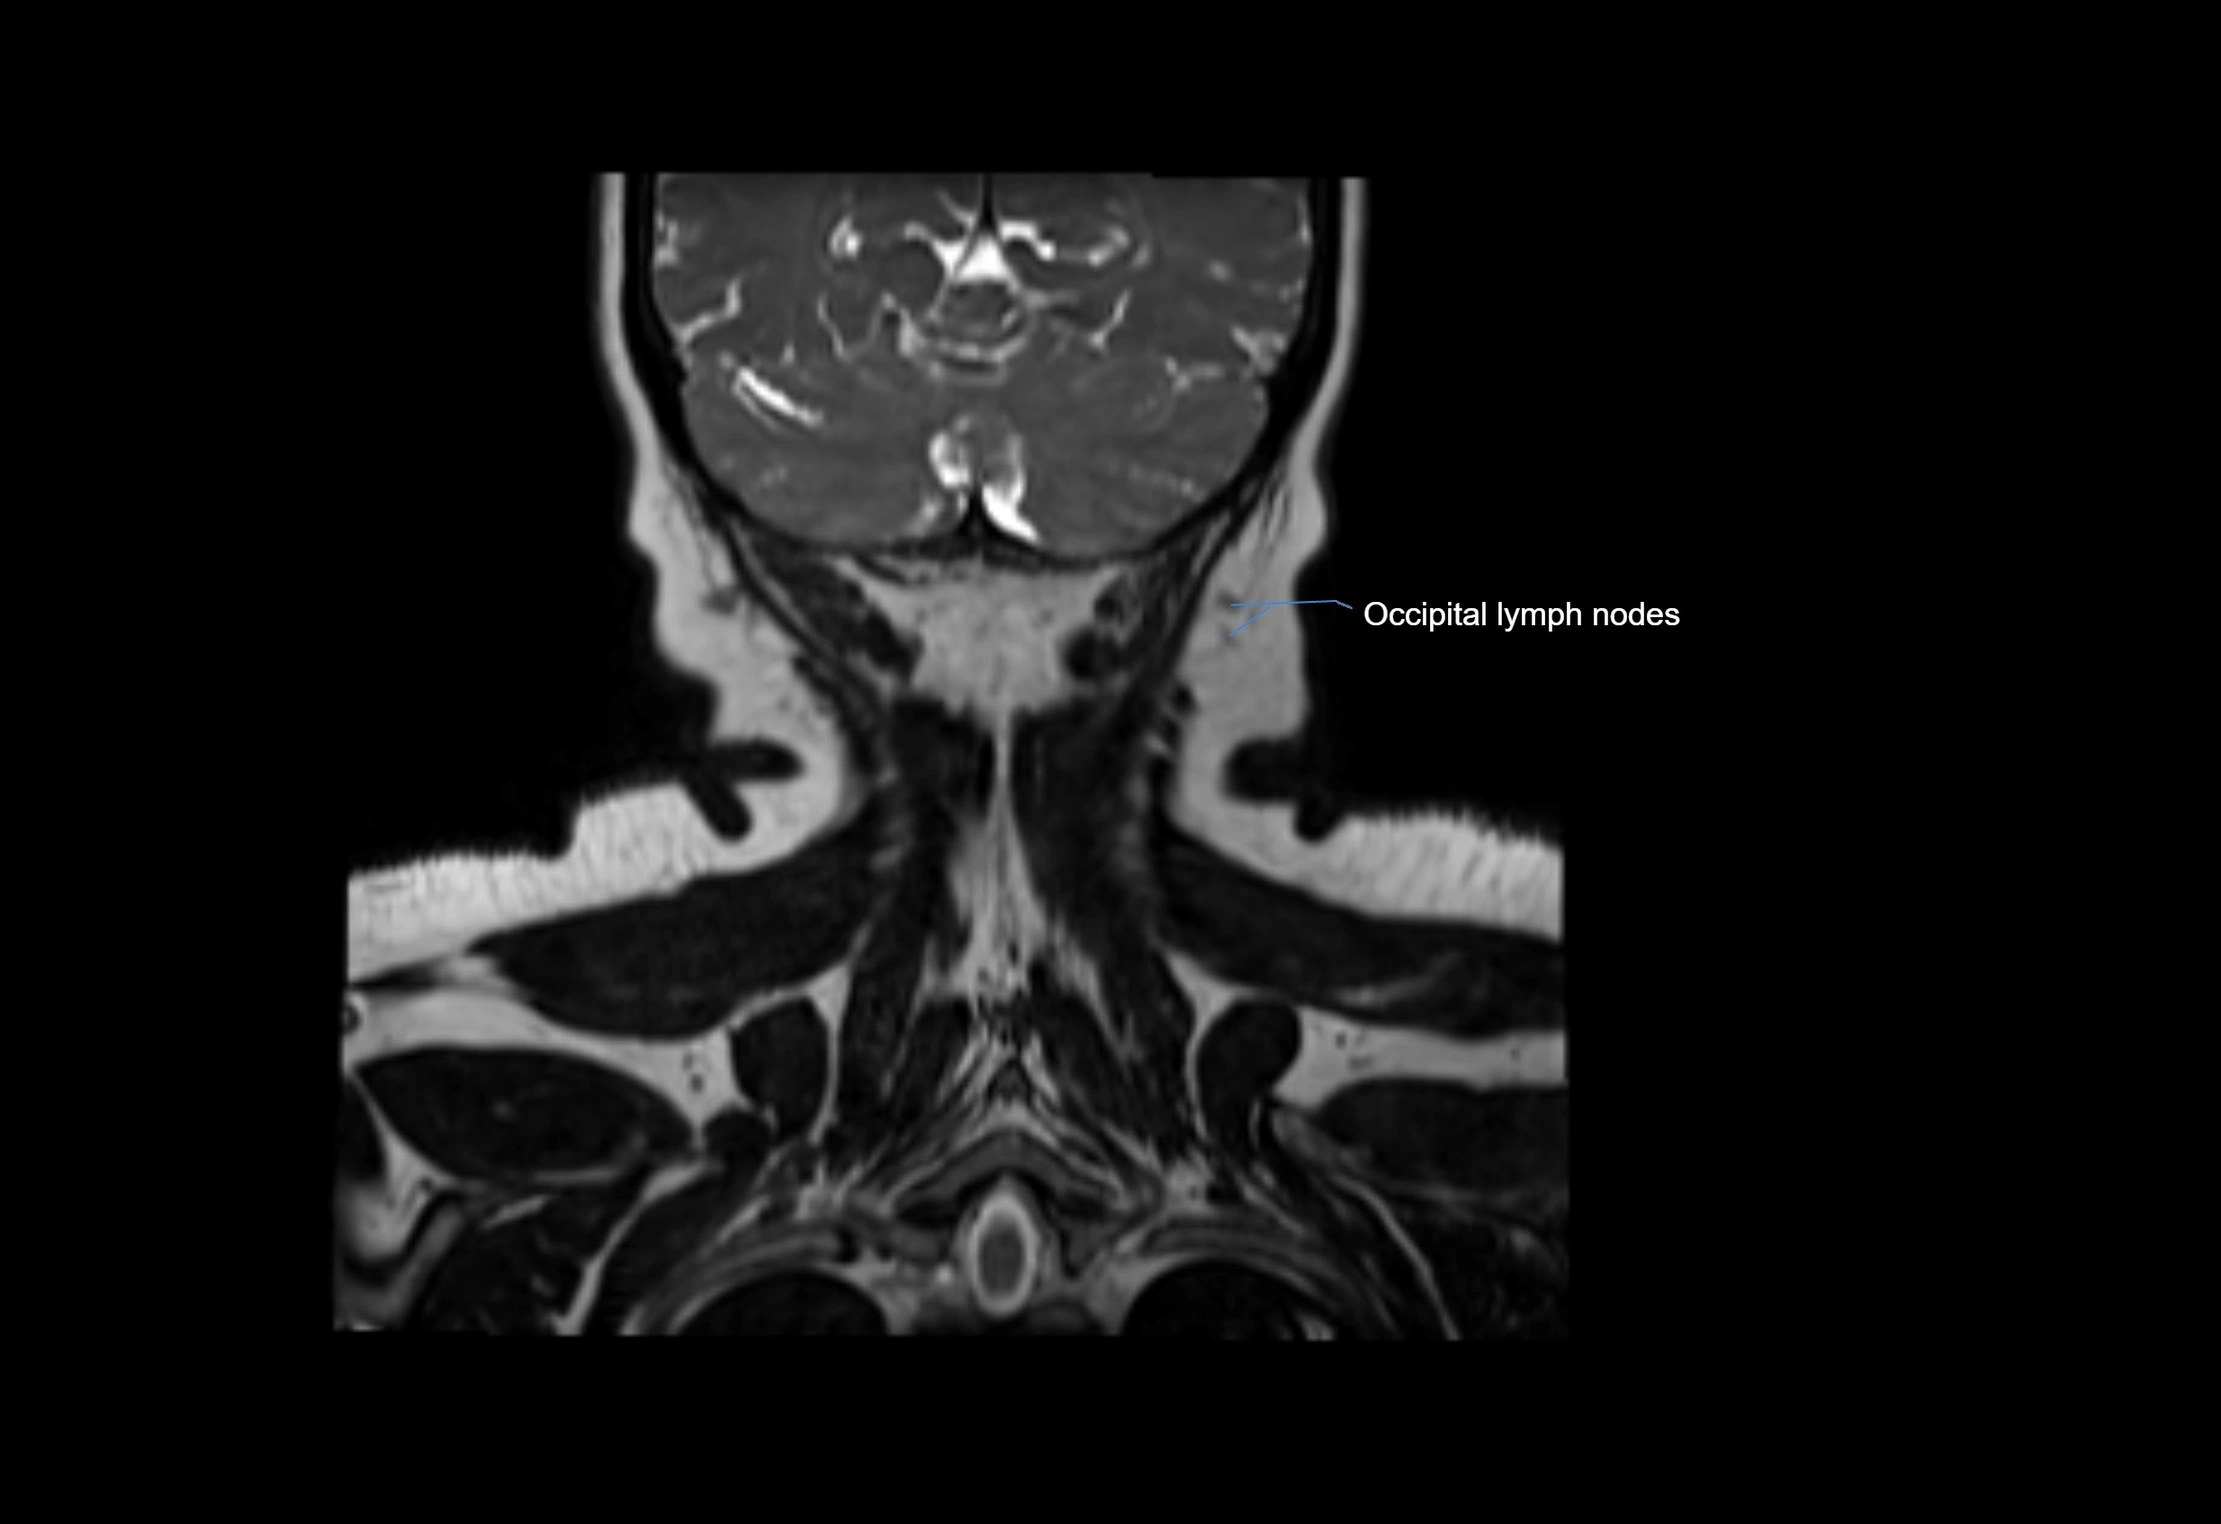

MRI Appearance

T2-weighted images:

• Nodes show intermediate signal, with surrounding fat bright

• Useful for detecting edema, inflammation, or infiltration

• Fatty hilum may appear slightly hyperintense relative to cortex

MRI images

image